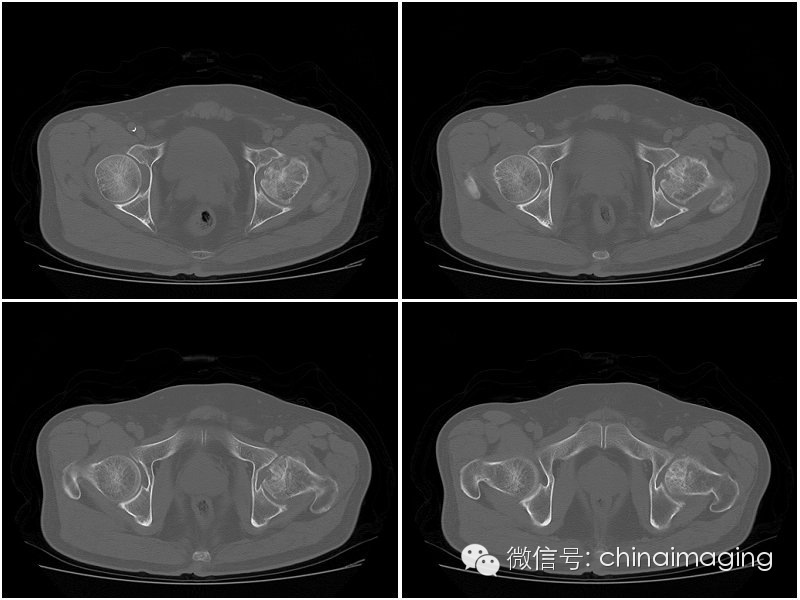

2股骨头坏死CT的表现

Ⅰ期 骨质无明显异常,但可有滑膜增厚,关节囊肿胀,关节腔积液,关节间隙相对增宽。

Ⅱ期股骨头形态正常无塌陷,正常时股骨头中心因持重应力的作用骨小梁生理性密度增高呈星芒征,当发现骨缺血性坏死时,星芒状骨纹间骨小梁吸收呈不均匀大眼状,由于反映性增生,使星芒状骨纹增粗、扭曲、浓密。

Ⅲ期此期称为塌陷前期,股骨头变平,股骨头前上部关节面下见窄细状透亮带,即半月征。

Ⅳ期 股骨头塌陷变形,股骨头内是不同程度囊变,周围有硬化或不规则,因塌陷所致的浓度区,可见碎骨片和关节游离体。继发退行性骨关节病,出现增生骨刺、关节间隙狭窄、关节半脱位。

股骨头塌陷

上图为IV期